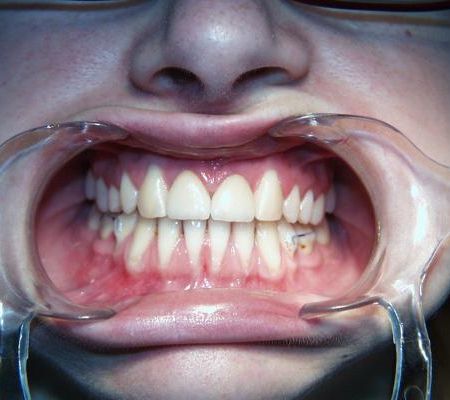

Nach der Behandlung

Die seitlichen Schneidezähne wurden nach Beendigung der aktiven Behandlung vom Hauszahnarzt mit laborgefertigten Keramik-Verblendschalen, sog. Veneers, verbreitert, die Eckzähne mit plastischem zahnfarbenem Füllungsmaterial und Beschleifen zu Schneidezähnen umgestaltet. Bei den im Unterkiefer ausgleichend entfernten beiden Zähnen handelte es sich um Milchbackenzähne, die keine bleibenden Nachfolger hatten. Auch diese Lücken wurden allmählich geschlossen, so daß die Seitenzahnreihen anschließend gut aufeinander paßten.